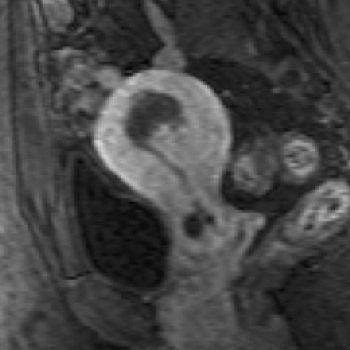

![]() |

| Same patient. Above, T2-weighted sagittal image obtained four months after treatment shows decrease in uterine size and junctional zone thickness, and new area of decreased signal intensity in region of adenomyosis. Below, contrast-enhanced T1-weighted sagittal image obtained during same study shows nonenhancement of this area, which signified devascularization in region of adenomyosis. Kitamura Y, Allison SJ, Jha RC, Spies JB, Flick PA, Ascher SM, "MRI of Adenomyosis: Changes with Uterine Artery Embolization" (AJR 2006; 186:855-864). |